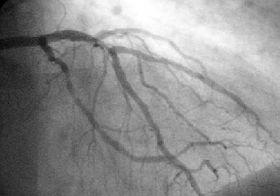

Coronary Angiography.